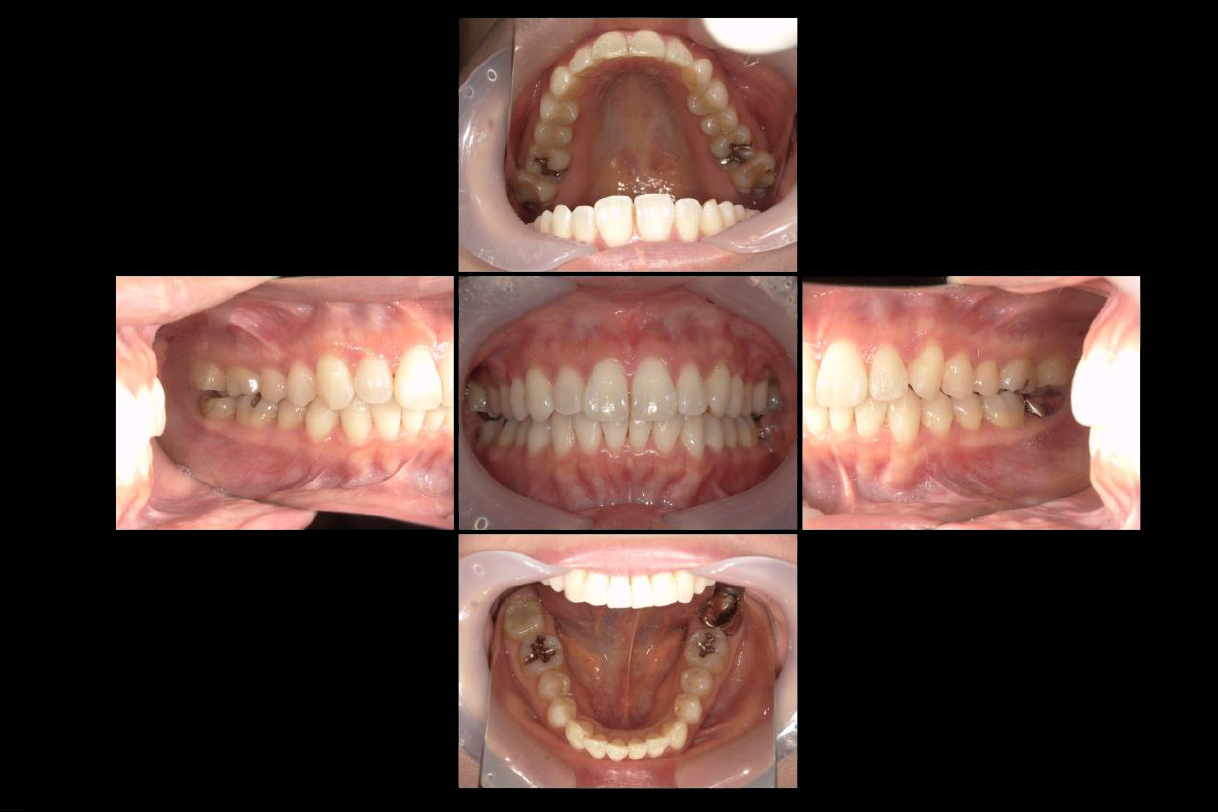

初診時年齢:40代男性

治療:全体矯正

治療法:マウスピース型矯正装置(インビザライン)

治療期間:3年

費用:902,000円(税込)

リスク・副作用:装置装着による違和感、歯の移動時の痛み